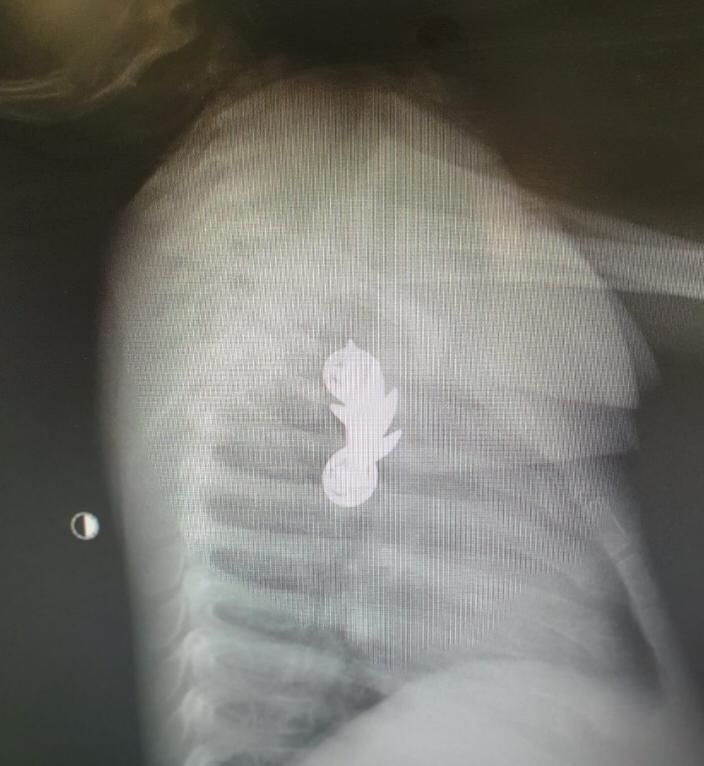

תינוק בן 10 חודשים בלע את סיכת הקצין של אביו ובפעילות מורכבת הצליחו בבית החולים קפלן לשלוף את הסיכה

צילום ממקום האירוע - תיעוד מבצעי מד"א ודוברות זק"א